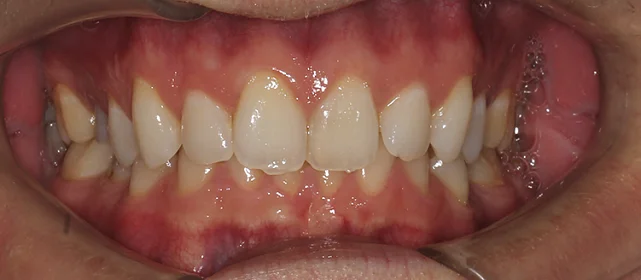

Нарушение соотношения челюстей и неправильное положение зубов — зубные ряды смыкались некорректно, зубы стояли со смещением.

Проблема: В клинику обратился мужчина с жалобами на неправильное положение зубов и смыкание — ряды сходились некорректно, зубы стояли со смещением. При этом было важно, чтобы лечение оставалось незаметным для окружающих, поэтому вариант с брекетами не рассматривался.

Решение: Поставили элайнеры Invisalign на обе челюсти. Лечение заняло 4 года — случай потребовал нескольких этапов коррекции, каждый из которых последовательно приближал зубы к нужному положению. Капы менялись каждые 1–2 недели, контрольные визиты — для отслеживания прогресса и выдачи новых наборов. Зубы встали на место, смыкание пришло в норму. Зафиксировали ретейнеры на обе челюсти, пациент направлен к ортопеду для завершающего этапа.

Случай потребовал нескольких последовательных этапов коррекции. Invisalign позволяет дозаказывать капы в рамках лечения, и здесь это понадобилось — каждый следующий этап доводил положение зубов точнее. Результат достигнут, прикус стабилен, ретейнеры на месте. Пациента направила к ортопеду.